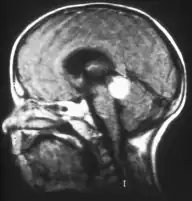

Inherited forms of retinoblastomas are more likely to be bilateral. In addition, inherited uni- or bilateral retinoblastomas may be associated with pineoblastoma and other malignant midline supratentorial primitive neuroectodermal tumors (PNETs) with a dismal outcome; retinoblastoma concurrent with a PNET is known as trilateral retinoblastoma.[13] A 2014 meta-analysis showed that 5-year survival of trilateral retinoblastoma increased from 6% before 1995 to 57% by 2014, attributed to early detection and improved chemotherapy.[14]

In about two-thirds of cases,[23] only one eye is affected (unilateral retinoblastoma); in the other third, tumors develop in both eyes (bilateral retinoblastoma). The number and size of tumors on each eye may vary. In certain cases, the pineal gland or the suprasellar or parasellar region (or in very rare cases other midline intracranial locations) is also affected (trilateral retinoblastoma). The position, size, and quantity of tumors are considered when choosing the type of treatment for the disease.

Traditional ultrasound B scan can detect calcifications in the tumour while high-frequency ultrasound B scan is able to provide higher resolution than the traditional ultrasound and determine the proximity of the tumour with front portion of the eye. MRI scan can detect high-risk features such as optic nerve invasion; choroidal invasion, scleral invasion, and intracranial invasion. CT scan is generally avoided because radiation can stimulate the formation of more eye tumours in those with RB1 genetic mutation.[24]

Aspect of trilateral retinoblastoma on MRI -